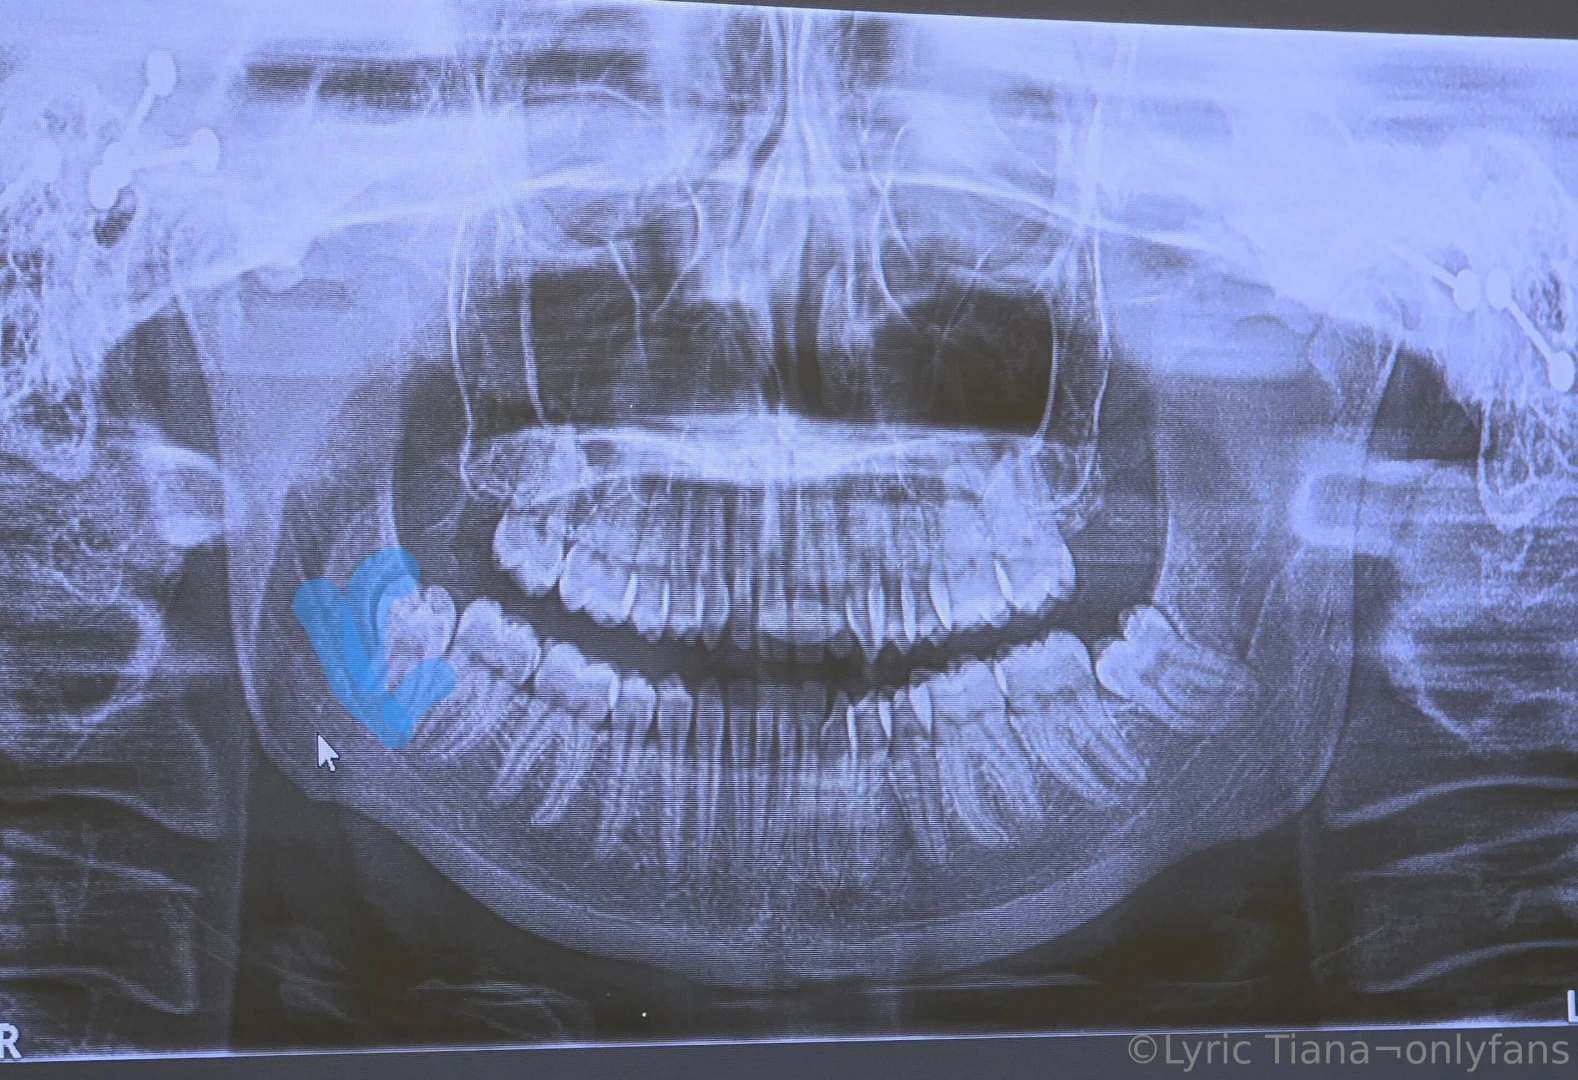

Hey everyone As you may or may not know I ve been sick since mid May I ve been to 5 different doctors 3 ERs and been diagnosed with loads of wrong things Finally last night in agonizing pain I came to the realization only a tooth can cause this much pain I went to the ER and demanded they check me for it and surprise surprise my right bottom wisdom tooth is severely infected Today I went to the emergency dentist and they said it s so badly infected it s into the two major nerves in my jaw I ve lost all sense of small and most of my sense of taste The dentist said it s so bad I m going to need to go to a specialty university clinic They re going to have to shave the infected bone which may cause it to break Everything in blue has to be removed or drained including the tooth This is very likely to cause permanent irreversible nerve damage I m so upset My doctors completely failed me on this I M the only reason they aren t still scratching their heads Insurance will only cover a portion of this dental work I m not sure what I m going to do as I ve been unable to work for weeks already If they break my jaw it ll be at least 6 more weeks Oh and they can t get me in right away